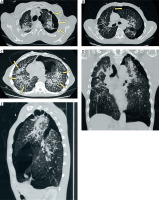

Figure 2

Computed tomography of the chest. A – Axial image showing a left-sided pneumothorax with pleural adhesions between the lung and chest wall (arrow). B – Axial image demonstrating mediastinal shift to the right, suggestive of a tension component (arrow). C – Axial image revealing diffuse and advanced silicotic changes with multiple parenchymal nodules (arrows). D – Coronal reconstruction illustrating the extent of pneumothorax. E – Sagittal reconstruction confirming parenchymal distortion and pleural involvement